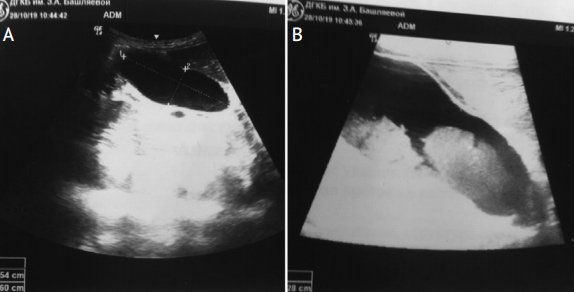

Диаметр общего желчного протока у детей первых 3 мес. жизни не должен превышать 1–1,2 мм. Как показали результаты УЗИ, проанализированных E. Fitzpatrick в 2010 г. у 878 детей первых трех месяцев жизни с холестазом, дилатация общего желчного протока более 1,2 мм (от 1,2 до 12,3 мм) была обнаружена в 9% случаев. На долю детей с синдромом сгущения желчи в этой группе приходилось 71,1%. Доказано, что дилатация общего желчного протока более 3 мм характерна для синдрома сгущения желчи (чувствительность 100% и специфичность 87%). Ниже мы приводим ультразвуковые признаки изменения желчи, полностью подтверждающие дословный перевод термина “Inspissated bile syndrome” – синдром «грязной желчи» (исследование проведено врачом отделения лучевой диагностики больницы им. З.А. Башляевой Ю.А. Бронниковой). На фотографиях с монитора (рис. 2А) видно, что содержимое желчного пузыря неоднородно, при внимательном осмотре обращает внимание осадок в области дна. Использование более чувствительного датчика и увеличение изображения на экране монитора (рис. 2B) позволяет более четко рассмотреть наличие осадка в желчном пузыре и подтвердить наличие синдрома сгущения желчи [22, 23].

Рисунок 2. УЗИ органов брюшной полости. Синдром сгущения желчи у девочки с врожденным пороком сердца

Figure 2. Abdominal ultrasound imaging. Bile thickening syndrome in a girl with congenital heart disease

А – в области дна желчного пузыря и частично стенок взвесь со слабой эхогенностью; В – изображение выполнено с помощью более чувствительного датчика, хорошо определяется неоднородная взвесь в просвете желчного пузыря (выполнено Ю.А. Бронниковой, врачом отделения лучевой диагностики больницы им. З.А. Башляевой).